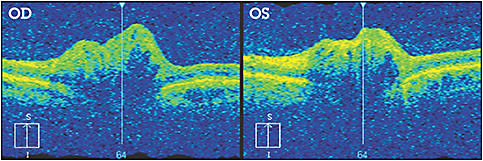

Figure 1: HM, a 52-year-old male, presented for his routine eye examination with a complaint of irritated eyes. His medical history was positive for hypertension. Best-corrected visual acuities were 20/20 OD and OS. Pupils were unremarkable. Bilateral ONHD that was previously diagnosed was observed. Visual field testing revealed stable peripheral defects and an enlarged blind spot. OCT testing also demonstrated mild RNFL defects (See Figure 2, page 25). The patient is being monitored closely with a three-month follow-up evaluation.

Figure 2: HM’s OCT image revealed the “lumpy-bumpy” internal contour of the ONHD.

• OCT. This is useful in detecting RNFL changes and OCT morphological changes associated with peripapillary neovascular membrane. It is also valuable in differentiating ONHD from optic nerve head edema, according to Archives of Ophthalmology. The most significant finding is that OCT of optic nerve edema reveals a smooth internal contour with a “lazy V” pattern, while ONHD display a “lumpy-bumpy” internal contour. Additionally, OCT enhanced-depth imaging allows evaluation of ONHD dimensions.